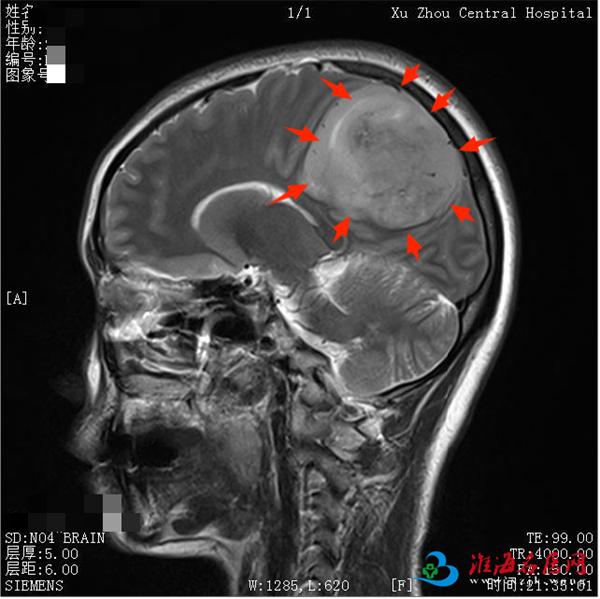

进一步检查发现,肿瘤直径达7厘米,体积接近成人拳头,位置特殊——它长在了大脑的“运动中枢”中央前回附近。

接诊医生、院神经外科董楠博士解释道:“中央前回是控制肢体活动的关键区域,肿瘤不仅侵犯了这一区域,导致患者出现下肢活动障碍,还对旁中央小叶造成推挤,并与颅内最大的静脉回流通道——上矢状窦紧密相邻。手术中一旦损伤这些重要结构,患者可能面临偏瘫、大小便失禁甚至生命危险。”

术后患者行颅脑MRI复查,结果显示肿瘤实现肉眼全切,中央前回区域得到良好保护,上矢状窦等重要血管结构保存完好,手术区域未见明确渗血或血肿形成。患者术前存在的下肢活动障碍得到有效缓解,力量恢复正常,目前已康复出院,准备接受后续治疗。